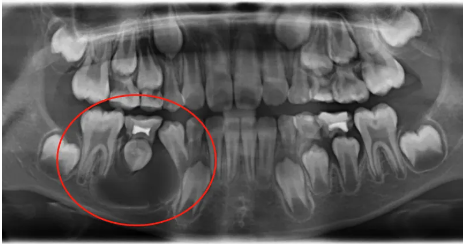

乳牙蛀牙如果发展成根尖周炎,局部的慢性炎症会影响继承恒牙的发育,有时还会引起牙源性的囊肿,可能最终导致多颗恒牙无法保留。

牙源性囊肿